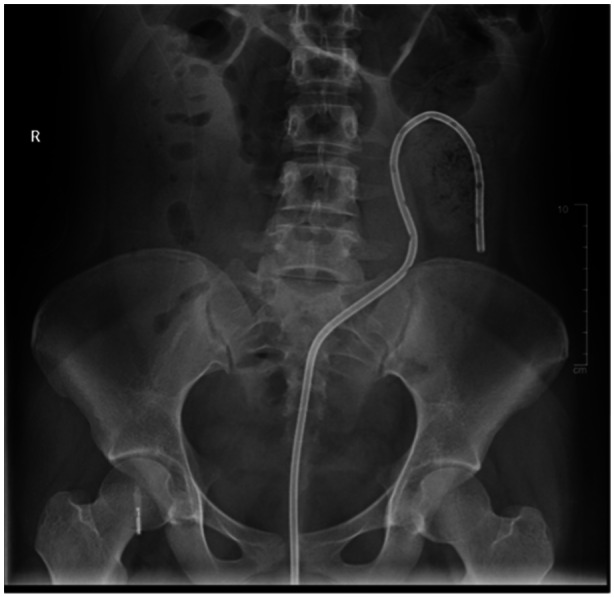

The process of the sigmoid colon twisting on its mesentery is known as sigmoid volvulus, a diagnosis rarely seen in the pediatric population. Volvulus can lead to blood flow obstruction of the colon and eventually perforation, necrosis, or sepsis. Predisposing factors include chronic constipation, chronic dysmotility, or Hirschsprung disease. This communication demonstrates three patients who presented to a tertiary pediatric care center with a diagnosis of sigmoid volvulus. All three patients underwent immediate endoscopic detorsion and rectal decompression tube placement. Two patients subsequently underwent surgical resection of redundant sigmoid colon. This communication highlights the use of sigmoidoscopy for detorsion of uncomplicated sigmoid volvulus with added support for initial rectal decompression tube placement, contributing to initial patient stabilization and positive patient outcomes.